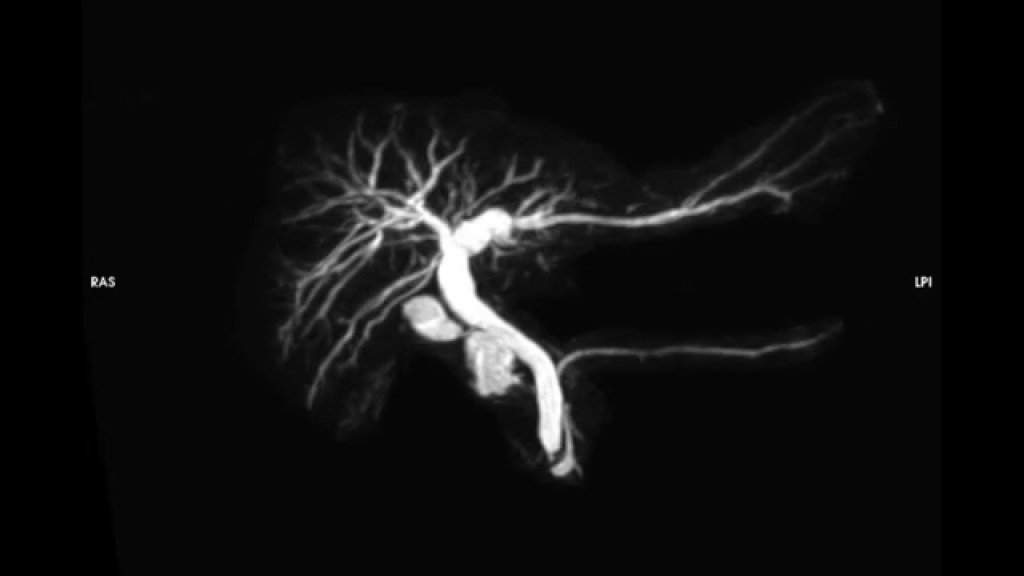

Магнитно-резонансная холангиопанкреатография (МРХПГ) – это вид магнитно-резонансной томографии (МРТ), который дает подробные изображения гепатобилиарной и панкреатической систем, включая печень, желчный пузырь, желчевыводящие протоки, поджелудочную железу и проток поджелудочной железы.

Метод позволяет заменить эндоскопическую ретроградную холангиопанкреатографию (ЭРХПГ). ЭРХПГ – это инвазивная диагностическая процедура, при которой врач при помощи эндоскопа вводит в протоки йодсодержащий контраст и выполняет рентгеновские снимки.